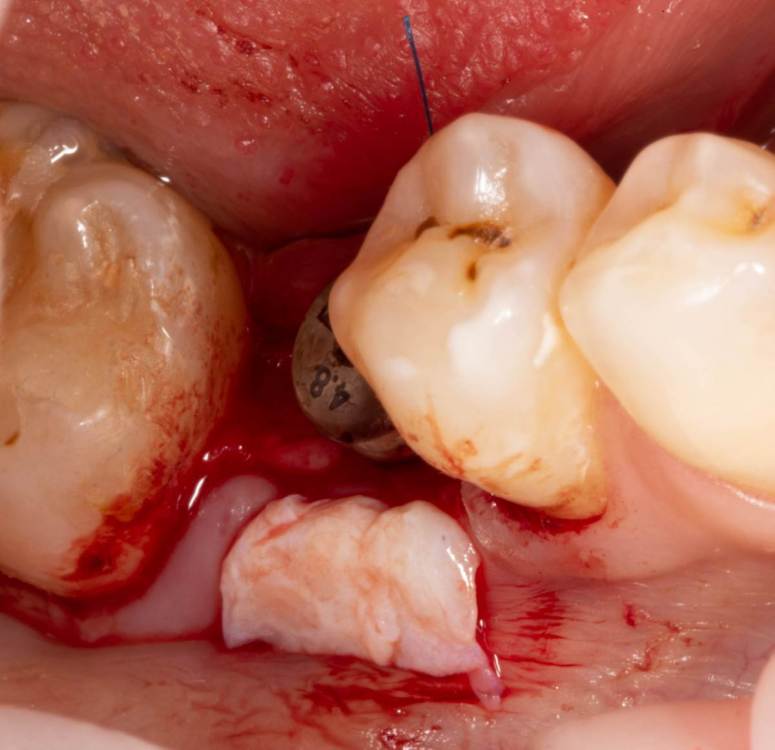

Женька Опубликовано 24 июня, 2023 Поделиться Опубликовано 24 июня, 2023 Собственно похожий случай. Разница лишь в том, что тут заглушка просвечивала. Предоп фоток, к сожалению, нет. 3.6*08мм, тк очень тонко было. Торк при установке потерял. Около 5 примерно был. В данном случае решил сст только вестибулярно положить. p.s. да, налёта много. Пациентка сестра моей одногруппницы, и чистит зубы только у сестры... при встрече я не думал, что чистки давно не было. Косяк, не отрицаю. Фотку со швами забыл сделать. Сделаем на снятии. Ссылка на комментарий

Женька Опубликовано 26 июня, 2023 Автор Поделиться Опубликовано 26 июня, 2023 @Fin корея. В отсутствии десны язычно. Кмк, эти проблемы я создал собственноручно. Неправильным разрезом и ушиванием, кмк опять же. @bakagaidzin в соседней теме про тл вообще сказали, что БЛ) и зачем так утопил Ссылка на комментарий

Женька Опубликовано 27 июня, 2023 Автор Поделиться Опубликовано 27 июня, 2023 Тут не стал сст сажать... тк при расщеплении язычно ниже платформы перфорировал лоскут( Подумал, что питания от перекинутого лоскута будет мало для сст. В первой теме-да, сст с двух сторон. Ссылка на комментарий